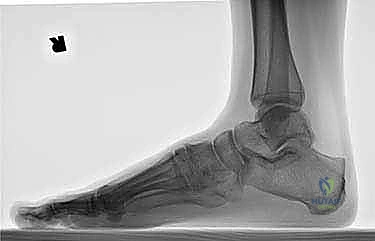

- الأشعة السينية أثناء الوقوف (Weight-bearing X-rays): وهي أهم أداة تشخيصية. الأشعة العادية والسرير فارغ لا تظهر المشكلة الحقيقية؛ يجب التقاط الأشعة والمريض يقف ليتحمل وزن الجسم، مما يظهر الانهيار الفعلي للمفاصل وتضيق المسافات بين العظام.

- الأشعة المقطعية (CT Scan): توفر صوراً ثلاثية الأبعاد للعظام، وهي ضرورية جداً للتخطيط الجراحي الدقيق وتحديد مدى التلف العظمي والزوايا المطلوبة للتثبيت.